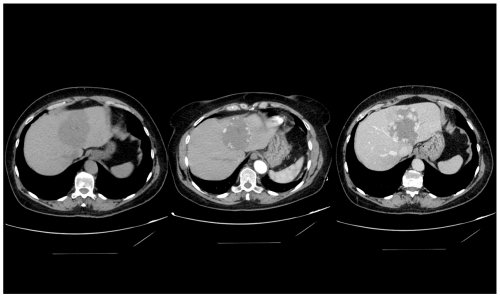

Hình 3. Hình ảnh u máu gan trái trên chụp cắt lớp vi tính